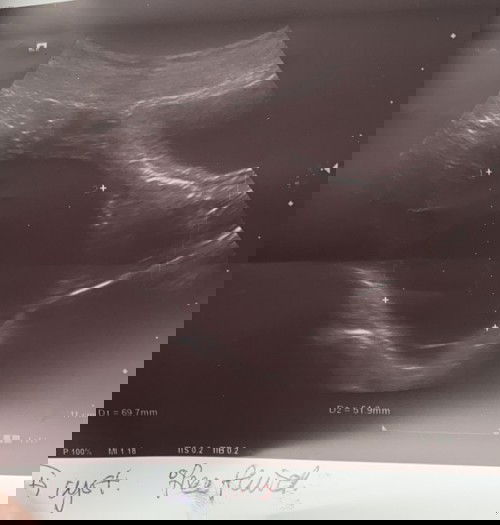

Cyst Besar Pada Awal kehamilan

Saya baru lepas scan baby , baby saya baru 5 weeks tapi saya dapat tahu saya ade cyst macam ni , doctor kata tak bahaya cuma doctor cakap kalau dia pecah & terbelit mungkin bahaya . so patut ke saya operate sebab takut effect nanti perut dah besar ? Sebab sekarang cyst tu sakit je , bila nak bangun sakit nak jalan pun sakit je 😢 #pleasehelp #1stimemom #advicepls